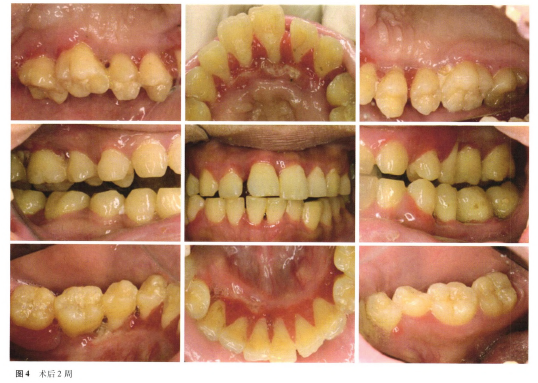

行切取活检,病理检查结果见图3,软组织炎症、水肿明显,可见结缔组织内有密集浸润的炎症细胞,以正常形态的浆细胞为主,呈片状或呈灶性聚集,伴少量的淋巴细胞,周围可见增生、扩张、充血的毛细血管及成纤维细胞。